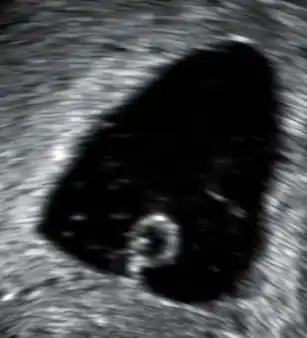

- Aborto retenido: se produce la muerte del embrión o feto, pero se retiene por un tiempo prolongado dentro del cuerpo de la madre. Suelen descubrirse durante los controles prenatales, notándose en la curva de crecimiento uterino la detención de esta y la ausencia de movimientos y latidos fetales.